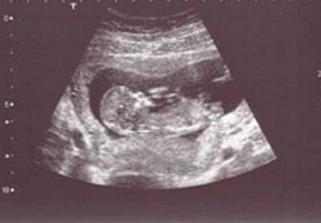

SRPŇÁTKA 2007 - fotky UTZ

album věnované mimískům, které se narodí v srpnu 2007 a jejich maminkám ze "Společného termínu SRPEN"